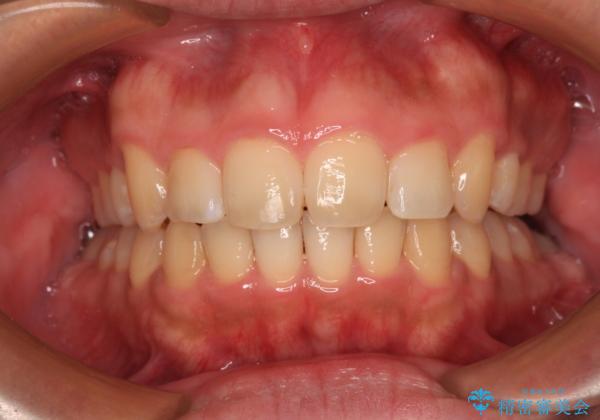

【モニター】後戻りで飛び出してきた前歯 ワイヤー装置での再矯正

- 学生時代に抜歯矯正した歯列が後戻りしてきたとのことで来院された患者様です。

舌の突出癖が原因で上顎前歯が前方に移動したと考えられたため、舌のトレーニングを徹底して行っていただきながら、後戻りを解消していくこととしました。

マウスピース矯正でもワイヤー矯正でも対応可能でしたが、患者様の希望によりワイヤー装置による矯正治療を行うこととしました。

ワイヤー矯正ということで、上顎大臼歯を後方に移動するための補助装置を併用して、積極的に前歯を引っ込めていくこととしました。

上顎歯列全体がスムーズに後方移動でき、1年で治療を終えることができました。